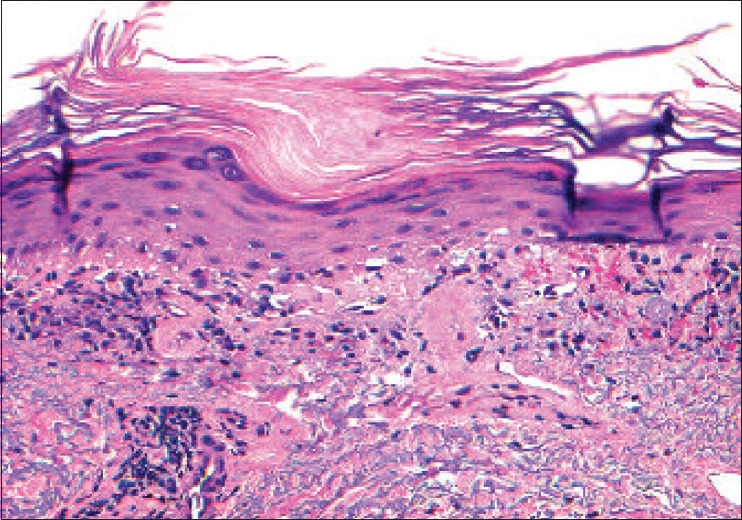

格雷厄姆-利特尔-皮卡迪-拉瑟尔综合征(GLPLS)的特征是弥漫性脱发和影响头皮、眉毛和三叉神经间区域的苔藓样毛囊性糜烂。它被认为是扁平苔藓的一种变异型。这种病通常先在躯干和四肢出现角化过度的丘疹,然后发展为脱发。有几种亚型的扁平苔藓与光敏性糜烂有关,包括类苔藓药物反应、光化性扁平苔藓和色素性扁平苔藓;但目前还没有与 GLPLS 相关的病例报道。我们在此报告首例显示光分布性苔藓样疹子的 GLPLS 病例,以扩大光加重病症的鉴别诊断范围。我们还通过这个病例回顾了病理生理学和治疗 GLPLS 的方法。

Graham-Little-Piccardi-Lasseur syndrome (GLPLS) is characterized by diffuse alopecia and a lichenoid follicular eruption affecting the scalp, eyebrows, and intertriginous regions. It is considered a variant of lichen planopilaris. The condition often begins as hyperkeratotic papules on the trunk and extremities followed by the development of alopecia. Several subtypes of lichen planus have been associated with a photodistriubuted eruption including lichenoid drug reactions, actinic lichen planus, and lichen planus pigmentosus; however, there are no reported cases associated with GLPLS. We herein report the first case of GLPLS displaying a photodistributed lichenoid eruption to expand upon the differential diagnosis of photoaggravated conditions. We also use this case to review the pathophysiology and therapeutic modalities to manage GLPLS.